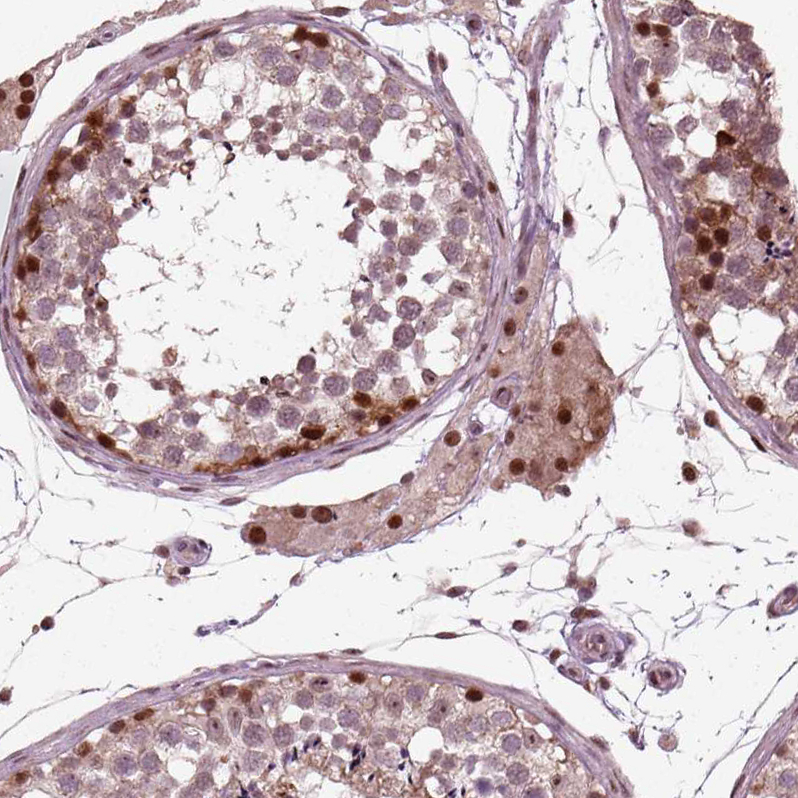

Immunohistochemical staining of human testis shows strong nuclear positivity in cells in seminiferous ducts.